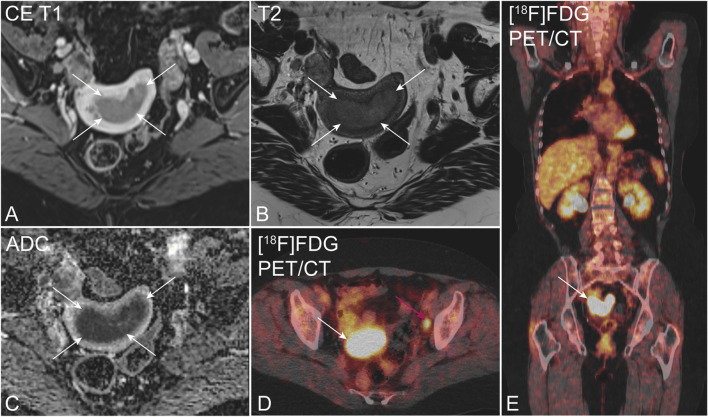

Fig. 1.

Preoperative pelvic MRI (A–C) and [18F]FDG PET/CT (D, E) in a 72-year-old patient with endometrial carcinoma, FIGO stage IIIC (endometrioid, grade G1). Axial oblique contrast-enhanced T1-weighted (A) and T2-weighted MRI (B) depicts an arcuately shaped uterine tumor (white arrows), exhibiting restricted diffusion at apparent diffusion coefficient map (C). Axial (D) and coronal (E) [18F]FDG PET/CT shows elevated [18F]FDG uptake both in the primary tumor (white arrow) and in a left iliac lymph node (cerise arrow)

All PET images were reviewed on an Oasis workstation (Segami Corporation) by one reader—in total, two nuclear medicine physicians, both with > 4 years of FDG-PET/CT experience. The reader was blinded to clinical, pathological, and patient outcome data as well as the FDG-PET/CT report and MRI findings. Increased FDG uptake (standardized uptake value (SUV) > 2.5) in primary tumor, lymph nodes (LNPET: yes/no), and suspected distant metastases (Fig. 1) were recorded in standardized PET registration forms. Finally, PET and the consensus MRI reading were merged with clinical, surgicopathological, and outcome data for further analyses.